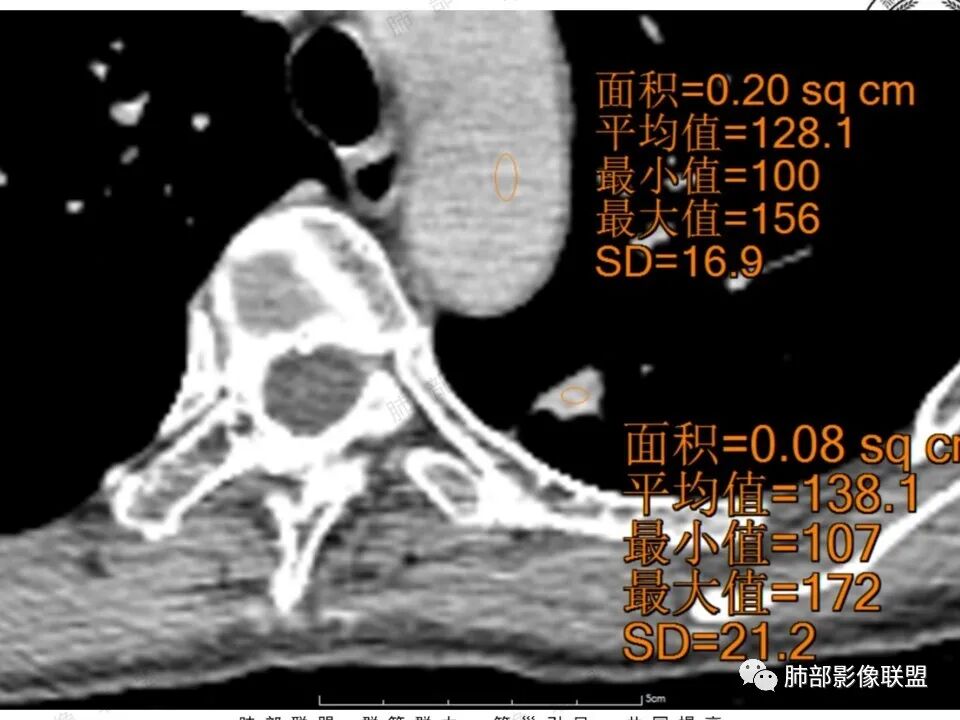

左肺上叶尖后段实性结节,边缘有清晰磨玻璃,胸膜有牵拉凹陷,明显强化,CT值超过主动脉,考虑血管畸形(周围磨玻璃可能是出血),鉴别IAC(影像表现符合,强化不符)

41岁女性,左肺上叶不规则结节,边缘见似清非清的磨玻璃影,叶间裂牵拉。整体病灶边缘平直,强化明显。另左上叶外侧尚有一磨玻璃结节(蘑菇兄弟?),考虑炎性肉芽肿可能性大。强化太明显让人很纠结,会不会存在CD,但边缘又有磨玻璃影;腺癌、结核、隐球都没有见过强化这么明显的,强化程度与主动脉基本一致,不会是动静脉畸形吧。

1.中年女性,体检发现;2.左肺上叶后段长条形结节灶,边缘有膨隆,也有收缩,腺癌和炎性结节都可以,但是周围见边界清楚磨玻璃影强烈提示腺癌可能性。3.显著强化的肺结节,无论如何都应当引起我们的高度重视!尽管炎性病灶和新生物都可以,尽管强化程度不能作为诊断癌肿的依据。

4.本例结节强化程度明显低于主动脉,也缺乏血管畸形的典型的迂曲结构,血管畸形可能性不大。